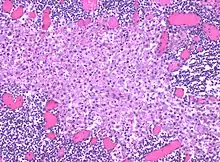

In medicine, histiocytosis is an excessive number of histiocytes[1] (tissue macrophages), and the term is also often used to refer to a group of rare diseases which share this sign as a characteristic. Occasionally and confusingly, the term "histiocytosis" is sometimes used to refer to individual diseases.

Histiocytosis is a rare disease, thus its diagnosis may be challenging. A variety of tests may be used, including: [5]

- Tissue biopsy and molecular testing to detect mutations